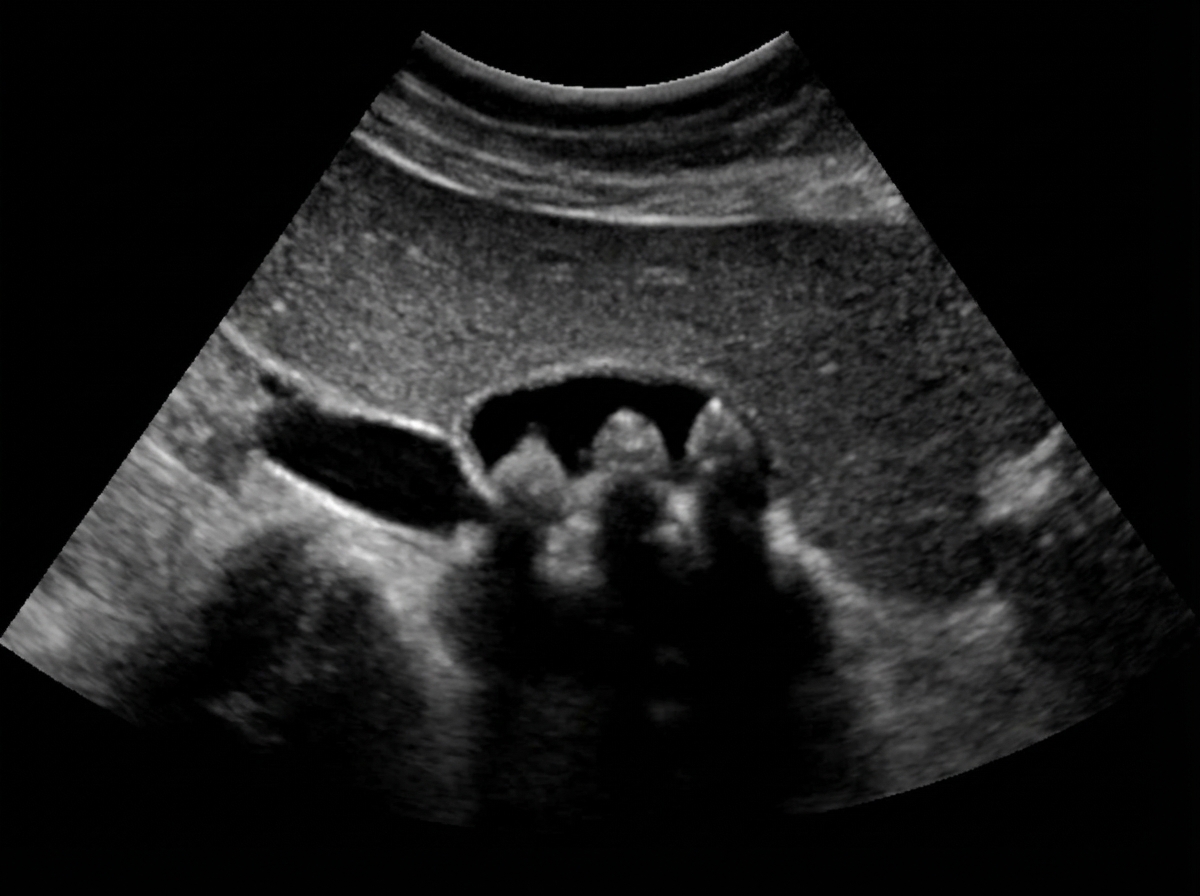

The image shows stones found in the gall bladder. Which of the following conditions is associated with their formation?

Explanation: ***All of the above*** - All three mechanisms work synergistically in **cholesterol gallstone formation**: **bile stasis** from hypomotility, **nucleation** of cholesterol crystals, and **mucus hypersecretion** as a scaffold. - The pathogenesis involves **Admirand's triangle** disruption (cholesterol supersaturation) combined with these promoting factors leading to stone precipitation. *Hypomotility of gall bladder* - **Bile stasis** from reduced gallbladder contractility allows prolonged contact time for cholesterol precipitation and crystal growth. - While contributory, this alone is insufficient without **cholesterol supersaturation** and nucleating factors for stone formation. *Accelerated cholesterol crystal nucleation* - **Nucleation** is the initial step where cholesterol crystals form from supersaturated bile, but requires additional factors for stone development. - This process alone cannot sustain **stone growth** without bile stasis and mucus glycoproteins acting as a binding matrix. *Hypersecretion of mucus* - **Mucus glycoproteins** provide a nucleating scaffold and binding matrix essential for cholesterol crystal aggregation and stone formation. - Although crucial for stone development, mucus hypersecretion requires **cholesterol supersaturation** and stasis to be pathologically significant.